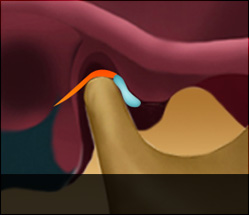

턱관절 디스크가 정상위치보다 앞으로 나와있는 상태입니다. 얼굴뼈와 턱뼈 사이에서 윤활작용을 해야 할 디스크가 앞으로 빠져있기 때문에 입이 잘 벌어지지 않고 입을 벌릴 때 통증을 느끼게 됩니다. 입을 크게 열면 앞으로 빠져있던 디스크가 턱뼈에 걸려 제자리로 돌아가며 ‘딱’하고 소리가 나는 경우와 입을 아무리 벌려도 디스크가 제자리로 돌아가지 못해 소리조차 나지 않는 경우로 나눌 수 있습니다. 얼굴의 근육과 인대 손상은 물론 목의 이상까지 동반하는 경우가 많기 때문에 수개월 이상의 치료가 필요한 경우가 대부분입니다.

정상디스크 위치

입을 다물고 있는 상태

입을 열고 있는 상태

정상 디스크 위치

디스크 전방전위1

입을 다물고 있는 상태

입을 열고 있는 상태

입을 열면 디스크가 제자리로

돌아가는 경우